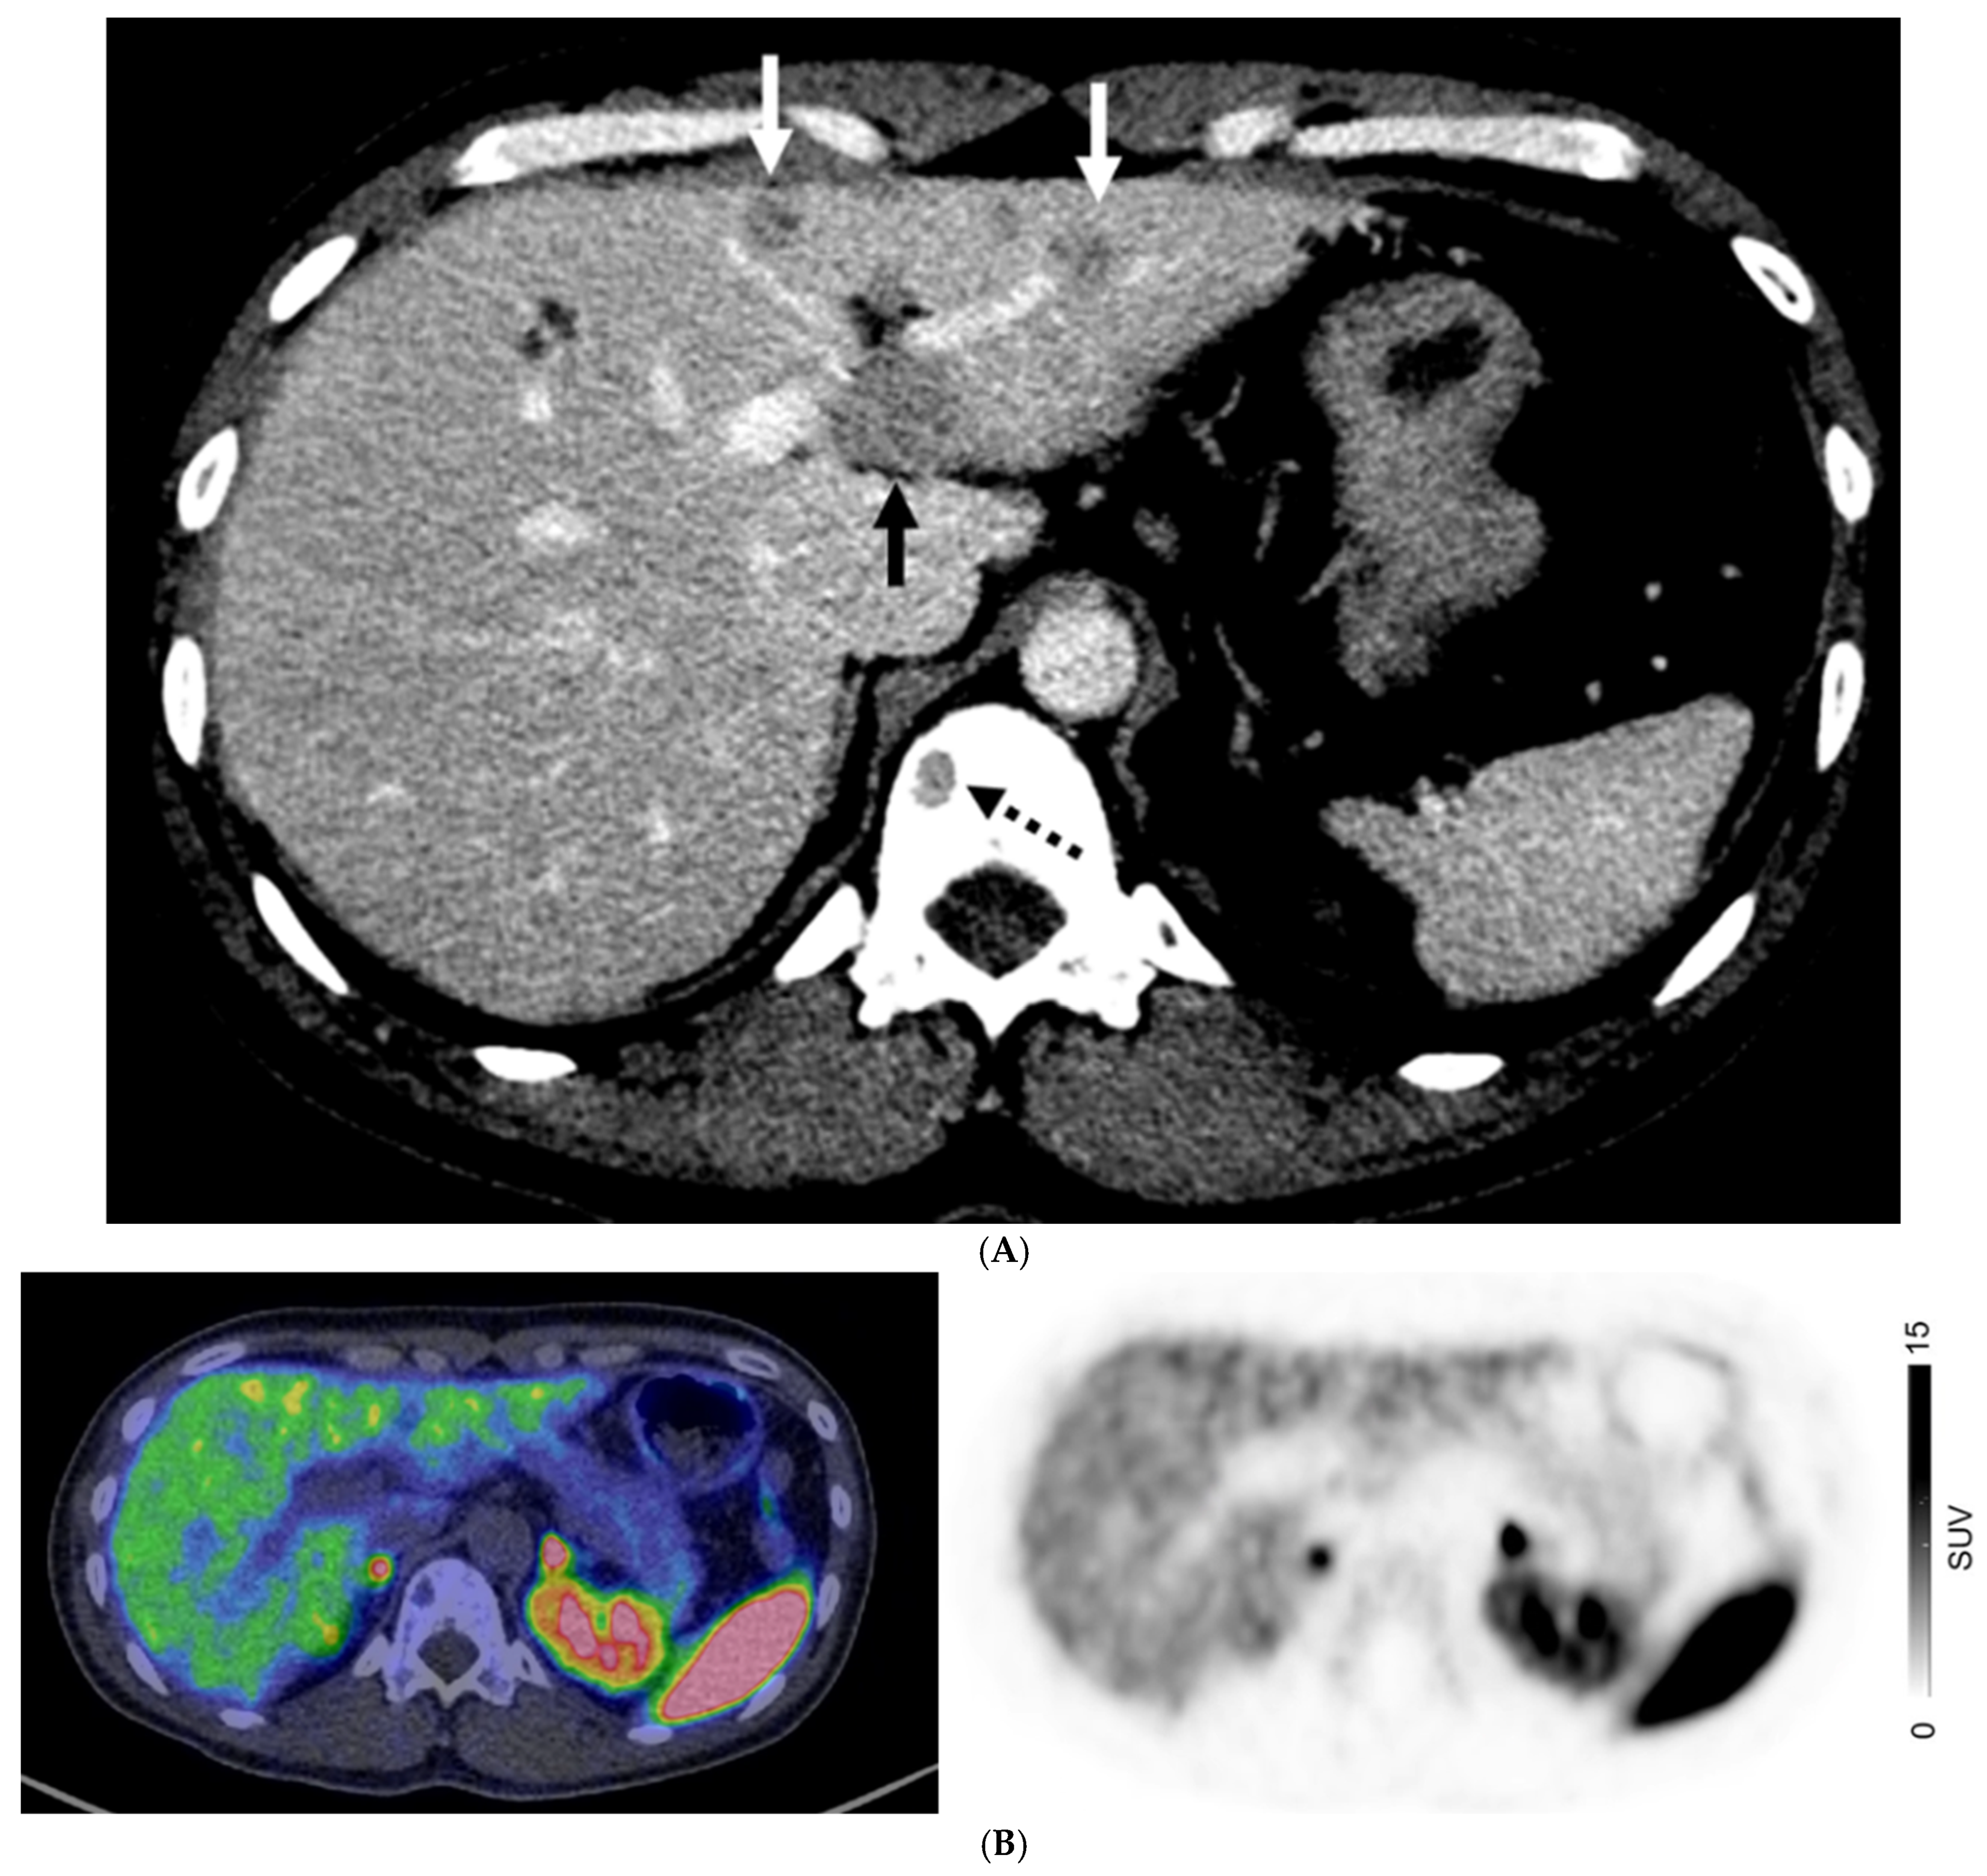

Figure 4.

A 40-year-old man with metastatic well-differentiated G3 neuroendocrine tumor, unknown primary. Contrast-enhanced CT ((A) Axial image) shows multiple liver deposits (histologically proven; solid arrows) and lytic bone lesion at T12 vertebral body (dotted arrow). 68Ga-DOTATATE PET/CT ((B) Fused axial PET/CT image left and Axial PET image right) show no corresponding focal radiotracer uptake.

For patients with non-GEP NETs, M0 was confirmed on both CI and PET in 56/104 (53.9%) patients. There were 25/104 (24%) with discordant M-stage on CI and PET. CI and PET suggested liver metastases in 34/104 (32.7%) and 23/104 (22.1%) patients, respectively, and extrahepatic distant metastases in 23/104 (22.1%) and 25/104 (24%) patients, respectively. There were 13/48 patients (27.1%) with non-GEP NETs who had distant metastases on CI but not on PET; 10 of whom had histologically proven distant metastases (Figure 4). When assessing the 47 patients with lung NETs, only 5/47 patients (10.6%) had a higher stage on PET, all of whom had bone metastases with or without liver metastases, while 6/47 (12.8%) had a higher stage assigned on CI, with metastases seen in the liver, lungs, and ovaries.